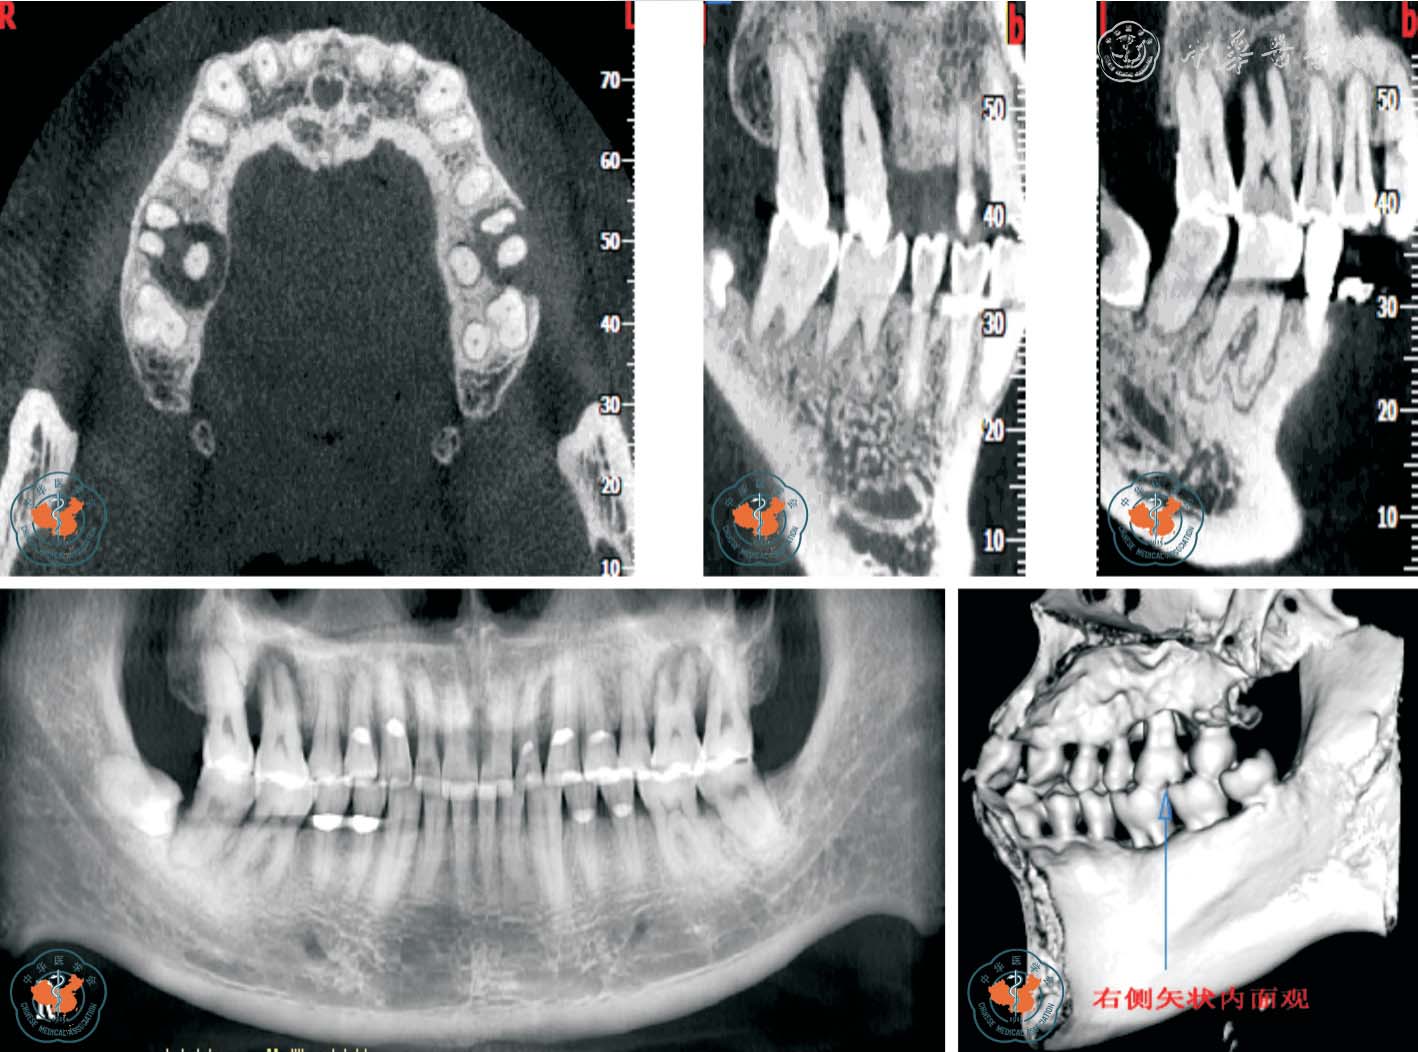

2. 观察牙根吸收情况:Tronstad12根据牙根吸收的起源部位将牙根吸收分为内吸收和外吸收,外吸收又根据不同临床表现分为炎症性外吸收、牙颈部外吸收和替代性外吸收。 早期牙根外吸收多无临床症状,X 线检查时才能发现。 由于根尖片只能显示相互重叠的二维影像,因此常不能清晰的显示吸收范围,难以准确评估牙根吸收的严重程度。 Estrela 等13报道指出根尖片识别牙根外吸收的假阴性率约为51.9%,假阳性率约为15.3%,尤其当病损位于颊侧或舌侧根面时,准确率更低。 而且,传统根尖片不能发现小于直径0.6 mm、深度0.3 mm的缺损。 CBCT 在很大程度上弥补了根尖片的缺点,其多层面重建(multiplannar reconstruction,MPR)技术可以显示病变的真实形态和部位,确定病变范围、破坏程度及周围牙槽骨的吸收状况,并可发现先前未发现的吸收缺损,有助于确定牙根吸收后的治疗规划,提高了患牙保存率(图3 ~4)。

图3 CBCT 轴位及MPR 重建显示上颌左、右第一磨牙牛牙症,其中左侧上颌第一磨牙根尖内吸收伴颊侧根折

图4 CBCT 轴位、VR、CPR 及MPR 重建冠、矢状位图像清晰显示根牙周病致牙根外吸收